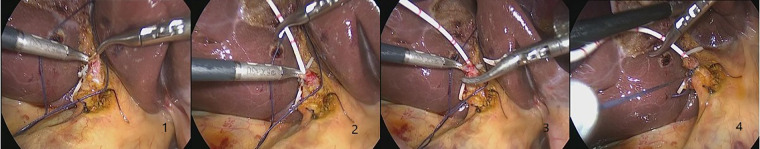

All the patients understood the surgical method and signed the surgical consent form. After removal of the CBD stones, the patients in C-tube group underwent primary suture of CBD with 3-0 absorbable sutures (Johnson, USA), and then C-tube was placed through the cystic duct stump and fixed with a sliding knot. The drainage tube was drawn and fixed under the costal margin of the right abdominal wall. The CBD incision and cystic duct stump were checked for no bile leakage, the procedure was illustrated by Figure 1. For the patients in T-tube group, T-tube was placed in CBD and closed with the same suture material, the drainage tube was also drawn and fixed under the costal margin of the right abdominal wall. Finally, a silicon drainage tube was inserted through the lateral trocar and fixed on the port of right anterior axillary line (ref. 9, ref. 11).

This study has also shown that C-tube inserted through the cystic duct had both therapeutic and investigative functions. It not only provided CBD drainage, but also served to inspect the CBD thus avoiding injury and confirming presence of stones. Intraoperative cholangiography through C-tube before choledochotomy could dynamically display the morphological characteristics of bile duct and the contractile function of Oddi’s sphincter, which provided more evidence to confirm the diagnosis of choledocholithiasis, and we called it a “supplementary inspection” for MRCP, CT and B-ultrasound. Usually, there are spiral-shaped folds (Heister valves) at the junction between the cystic duct and the common bile duct, which will be the barrier for C-tube insertion (ref. 22). Inserting C-tube through cystic duct with Laparoscope is a delicate process that requires proficient surgical skills, therefore, we recommend that this type of surgery should be performed by professional hepatobiliary surgeons, meanwhile, surgeons are encouraged to attend the training of LCBDE to reduce the chances that they may seek for help when dealing with difficult CBD stones (ref. 13). Our experiences from this study including (Figure 3): 1. When the surgeon inserts the catheter through cystic duct, it is necessary to adjust the direction of the cystic duct and maintain proper tension to avoid violent manipulation. The depth of the insertion is about 5.0 cm to avoid passing through the odds’ sphincter, C-tube drainage will maintain equivalent to the height of the bile column with normal biliary pressure, external drainage will be “automatic” only when the biliary pressure is higher. Under normal circumstances, the bile enters the intestine along the normal channel through Oddi’s sphincter, which effectively avoids the loss of a large amount of bile. C-tube can be closed and removed at an early stage. 2. The C-tube is always ligated and fixed with a slip knot (Duncan knot) (ref. 23). When tightening the knot, surgeons should not over-tighten it so as to maintain the patency of the drainage tube, however, pipe slippage may be caused by a loose knot. Meanwhile, The Duncan knot can ensure the rapid closure of the cystic duct and avoid bile leakage when the drainage tube is pulled out. 3.After the peak of biliary edema 3 days after operation, patients with C-tube drainage underwent postoperative cholangiography to observe the morphology and function of the biliary tract.